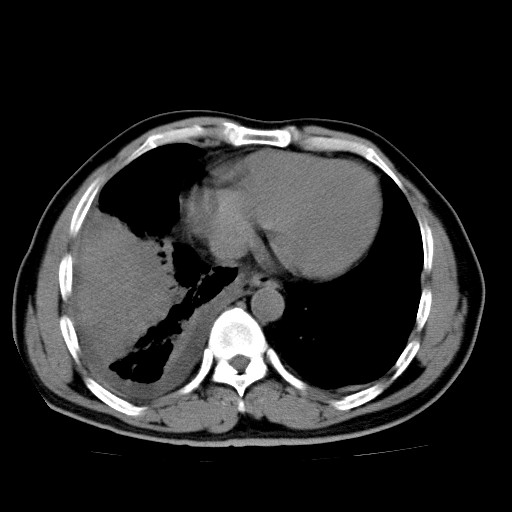

男,54岁,咳嗽,右侧胸痛10天。肺窗>150k,传不了

右中央型肺癌并右肺下叶不张,纵隔内及右胸膜转移,右胸腔积液

考虑   右肺癌伴右下肺部分不张,阻塞性肺炎,纵隔淋巴结增大,右侧胸腔积液其他待排

右下叶大片实变,肺门未见明显肿块影。有胸腔积液和纵隔内肿大淋巴结影。没有增强和肺窗,不好定。

右下叶大片性阻塞性肺炎,肺门未见明显肿块影,纵隔内可见肿大淋巴结影,右见右侧胸腔积液及右侧胸膜增厚。

考虑:右侧中心性肺癌?伴纵隔淋巴结转移。建议上传肺窗。